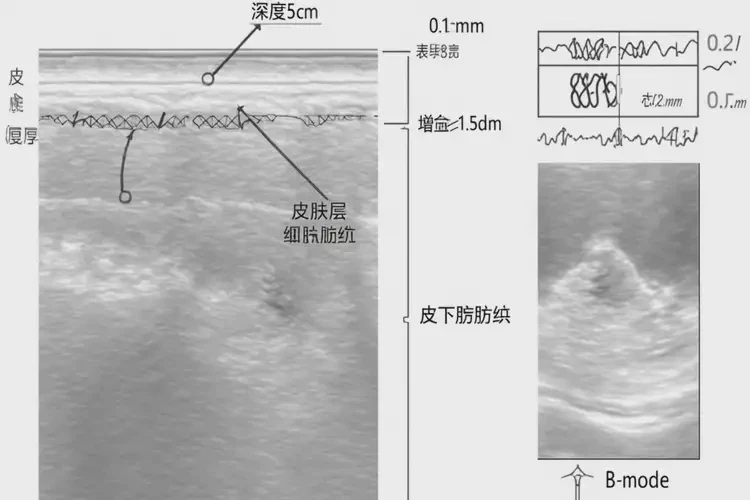

2. 超聲檢查

高頻超聲可以評(píng)估皮膚的厚度、血管分布炎癥程度,幫助醫(yī)生確定玫瑰痤瘡的治療方案